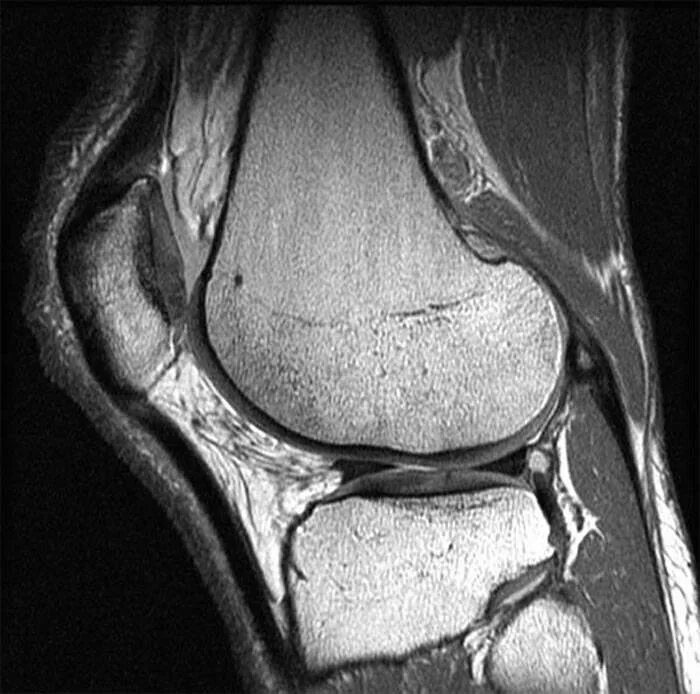

Мрт суставов кемерово